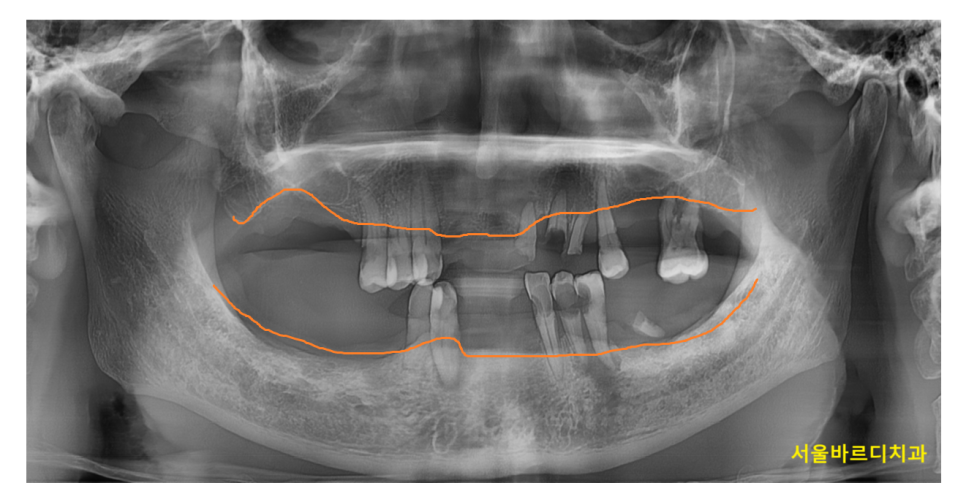

240423 풍치로 다수의 치아 상실

상일동 치과에 다수의 치아가 상실되어 내원한 환자분입니다.

처음에는 하나 둘 치아가 흔들리더니

겉잡을 수 없이 치아가 빠졌다고 하셨는데요.

풍치의 무서운 점이 이런 부분 때문이죠ㅠㅠ

하나를 건들이면 모두가 무너지는 도미노처럼

잇몸은 서로 연결되어 있기 때문에

하나가 빠지면 균형이 무너집니다.

240425

잇몸뼈는 특정 부위가 내려갈 수도 있지만

일반적으로는 전반적으로 조금씩 조금씩 내려가서

문제가 한번에 나타납니다.

때문에 치아 한두개가 흔들리면

잇몸에서 신호를 보내고 있는겁니다.